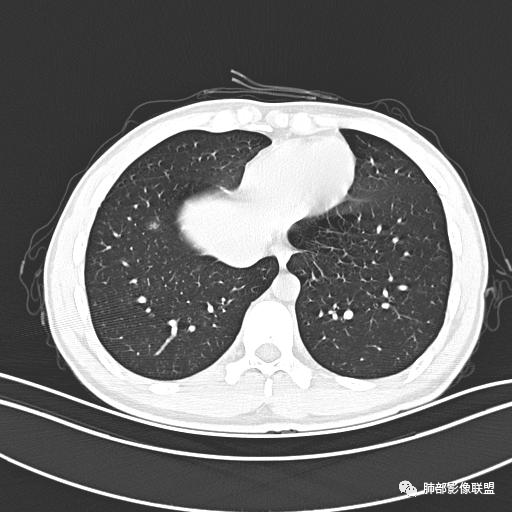

小强:青年,发热,皮疹;双肺散在结节,周围磨玻璃,点晕征,疱疹病毒感染,鉴别荚膜组织胞浆菌,结核。 大雄:青年,急性起病,发热伴全身皮疹2天,抗病毒治疗体温有下降。双肺随机分布大小不等类圆结节,“点晕征”。考虑水痘-疱疹病毒(VZV)血播询问接触史,查体皮疹分布以及形态基本可诊断。 王开金江津中心医院呼吸科:青年男性,起病急,病程短,以发热,皮疹为首发症状,感染指标以单核细胞升高为主,胸部ct双肺多发结界,周围有晕,点晕表现,随机分布,同意於老师意见,水痘疱疹病毒血流感染累及肺。 王秀仙:双肺多发大小不等结节,周围有晕,边缘模糊,呈点晕征表现。青年,急性起病,发热伴全身皮疹2天,抗病毒治疗体温有下降。考虑疱疹病毒。鉴别荚膜组织胞浆菌。 傅昌瑜:19岁男性,发热、全身皮疹2天,单核细胞增高,双肺多发结节,结节边缘见边界不清磨玻璃影。点晕征+发热、全身皮疹+单核细胞增高——考虑水痘-带状疱疹病毒肺炎。 一切∮随缘:年轻男性,发热,皮疹两天,实验室,CRP,PCT增高,影像:双肺多发散在磨玻璃结节,边界欠清,大小不等,呈点晕征改变,以血管束周围分布为主,局部血管束略增粗,其它无明显改变,考虑:1:病毒性肺炎(水痘疱疹病毒?不知道皮肤有无改变)2:真菌(组织胞浆菌,血管侵袭性肺曲霉)3:GPA4:寄生虫(实验室没有看到嗜酸细胞增高) 赵山河:双肺散在结节,周围有晕,边缘模糊,呈点晕征表现。青年,急性起病,发热伴全身皮疹2天,抗病毒治疗体温有下降。考虑水痘—疱疹病毒感染。洪桥爱:青年男性,发热、皮疹2天,伴瘙痒,皮疹于面部首发,之后进展至全身,虽然没有对皮疹进行描述,但是从出疹时间及皮疹进展情况,伴瘙痒,应该就是个水痘患者;CT提示双肺随机分布结节影,部分结节伴有边界不清晕征,考虑水痘血播肺。 刘强:年轻男性,急性起病,皮疹,发热,抗感染治疗体温下降,说明有效。影像表现为散在点晕征,感染类疾病谱(疱疹病毒,真菌,结核),结合年龄,皮肤皮疹,考虑水痘-疱疹病毒性肺炎。 小兜:男性,19岁,发热皮疹两天,颜面部至全身,CRP,降钙素及单核增高。CT示双肺散在小结节,周围伴磨玻璃影,点晕征,考虑为水痘-带状疱疹病毒(varicella-zoster virus,VZV)肺炎 必有路:青年,皮疹+发热+“点晕征”→水痘-疱疹病毒(VZV) 许慧良:青年男性患者,发热、皮疹2天,体温最高38.5℃,第3天皮疹扩展至全身,伴瘙痒,胸部CT:双肺多发随机分布的小结节,结节周边见边界模糊的晕征,考虑水痘病毒感染流心明智:男,19,急性起病,发热伴全身皮疹2天。出疹顺序头→全身,抗病毒有效。胸部CT:两肺多发大小不等类圆形实性小结节影,随机分布,结节周围环绕GGO,边界模糊,呈点晕征。出疹特点是关键,未提示。考虑:血播病毒性肺炎,水痘-疱疹病毒?麻疹?鉴别荚膜组织胞浆菌、TB、血管炎、寄生虫等。 浪迹天涯:病灶多为5-10mm大小结节,结节周围可见磨玻璃样的晕环,常多发,可分布于肺内任何区域,考虑水痘—带状疱疹病肺炎如果短时间内有新的一个区域浸润,更加能说明,